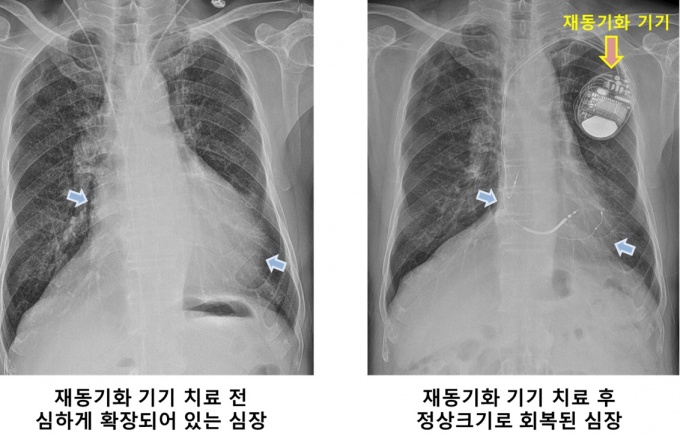

심장재동기화치료는 환자 몸 속에 삽입한 재동기화기기와 연결된 전극선을 심장의 우심방과 우심실, 좌심실 외측 벽까지 세 곳으로 밀어 넣은 뒤 전기를 흘려보내 비정상적 신호와 비대칭적인 심장 수축을 바로 잡는 치료법이다.

시술이 어려운 만큼 치료 효과도 극적이다. 심장 기능이 100점 만점 기준으로 50점에서 60점에 불과하던 환자들이 해당 치료를 받고 나면 70점에서 80점까지 호전된다. 이 가운데 3분의 1은 거의 정상 수준에 가까워지기도 한다.